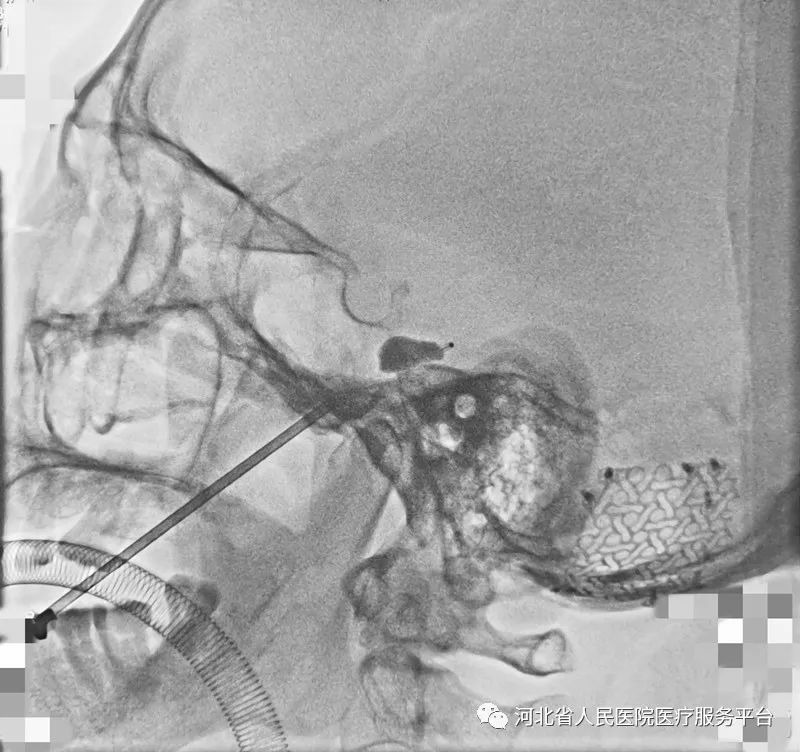

图为刘先生的手术图像